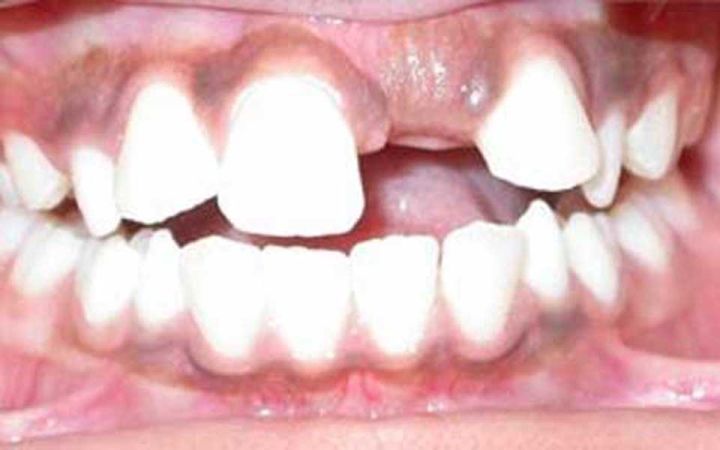

最为常见的是上颌切牙的迟萌。乳切牙因为外伤、蛀牙等原因,造成了过早脱落,致使牙龈反复摩擦增厚,导致下面的恒牙萌出困难,此时需要去进行牙齿助萌。

上颌切牙迟萌